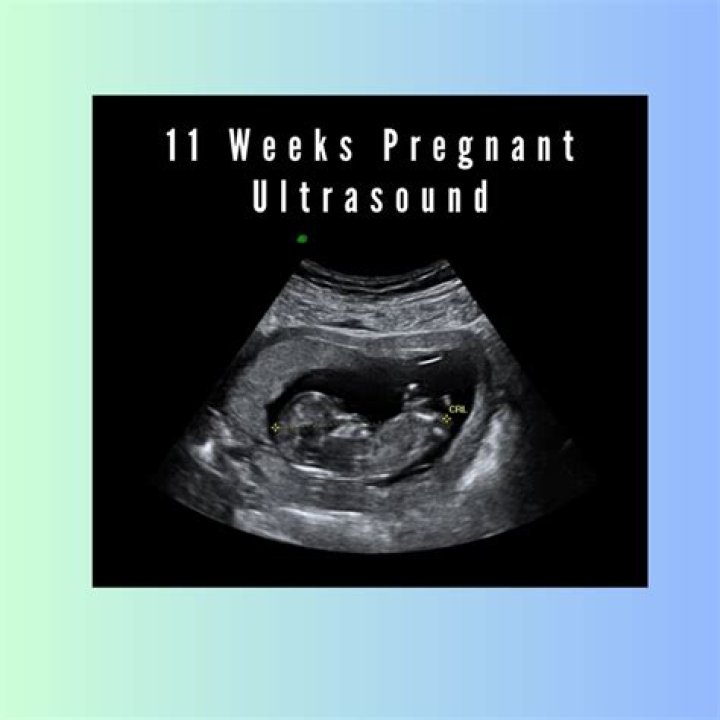

Where is the baby in the womb at 11 weeks?

Baby-to-be is lying on her back with her head on the left side of the image and her legs pointing up. From this image, you can see that her neck is growing, separating her large head from the rest of her body. Her head still makes up more than 50% of her body size, which is normal.